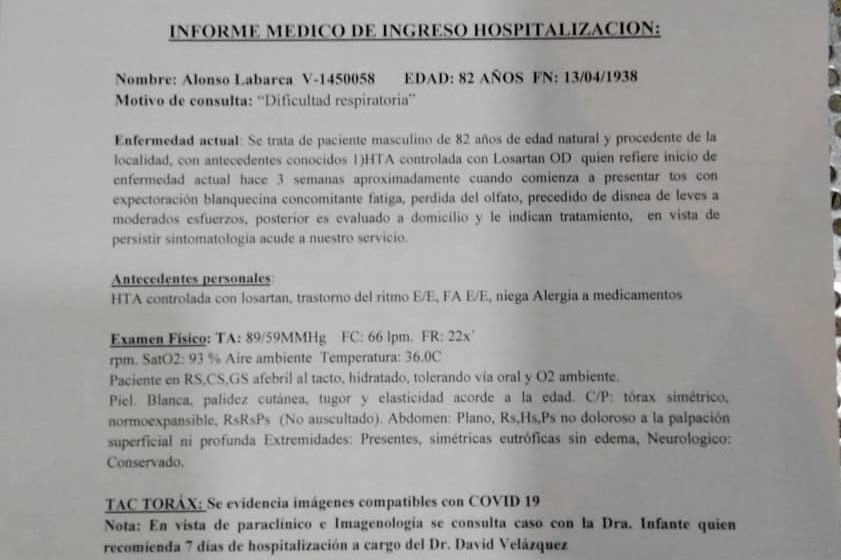

El 31 de agosto mi padre fue diagnosticado con neumonía bilateral vinculada al Covid-19. Si bien le aplicamos el tratamiento en casa, el lunes 14 tuvo que ser hospitalizado porque la infección respiratoria no cedía. Ahora, el médico tratante recomienda 5 días de terapia intensiva ante fallo respiratorio y hemodinámico, por bradicardia extrema, con falla multiorgánica por sepsis.

Con los cuidados intensivos, los costos se incrementan considerablemente. A los 3.600 dólares iniciales por la hospitalización se suman otros 10.000 dólares más las medicinas y demás cuidados que necesita (adjuntos los informes y presupuestos).

On August 31, my father was diagnosed with bilateral pneumonia linked to Covid-19. Although we applied the treatment at home, on Monday the 14th he had to be hospitalized because the respiratory infection did not subside. Now, the treating physician recommends 5 days of intensive therapy for respiratory and hemodynamic failure, for extreme bradycardia, with multiorgan failure due to sepsis.

With intensive care, the costs increase considerably. To the initial $3,600 for the hospitalization is added another $10,000 plus the medicines and other care he needs (reports and estimates attached).

El 31 de agosto mi padre fue diagnosticado con neumonía bilateral vinculada al Covid-19. Si bien le aplicamos el tratamiento en casa, el lunes 14 tuvo que ser hospitalizado porque la infección respiratoria no cedía. Ahora, el médico tratante recomienda 5 días de terapia intensiva ante fallo respiratorio y hemodinámico, por bradicardia extrema, con falla multiorgánica por sepsis.

Con los cuidados intensivos, los costos se incrementan considerablemente. A los 3.600 dólares iniciales por la hospitalización se suman otros 10.000 dólares más las medicinas y demás cuidados que necesita (adjuntos los informes y presupuestos).